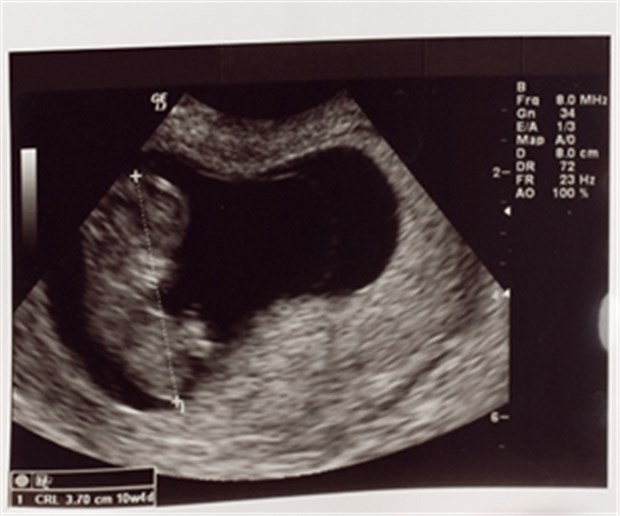

Geht's ihm gut? Bei ACE-Hemmern heißt es Vorsicht.

© Artur B. / panthermedia.net